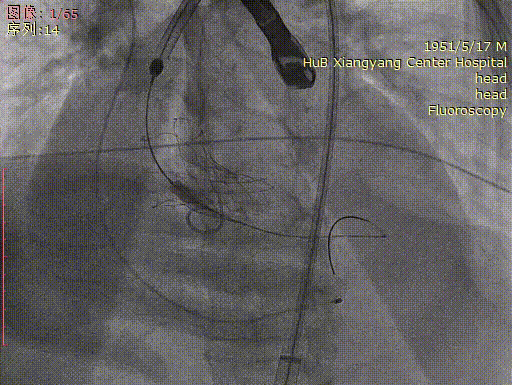

主动脉根部造影

房间隔穿刺跨瓣

按压下完成球囊预扩

按压下完成瓣膜释放

释放后恢复心跳

最后造影